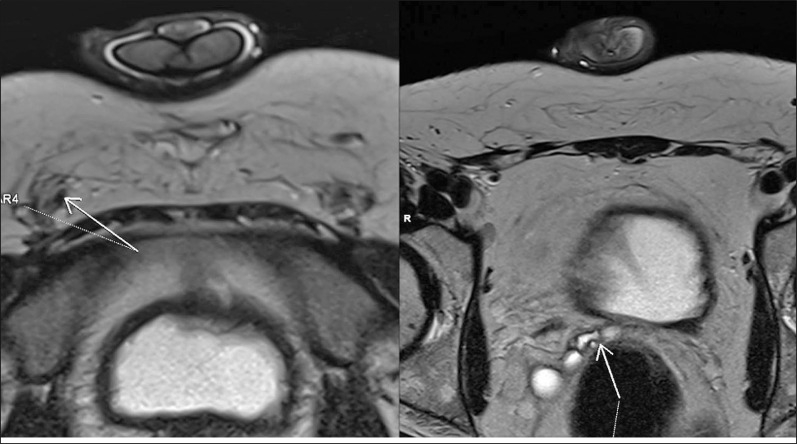

无精子症在10-15%的男性中被诊断为不孕症。梗阻性无精子症发生率为20-40%,其特征是卵泡刺激素值正常,睾丸大小正常,附睾增大。梗阻性无精子症是男性不育的常见原因。几种成像技术用于评估精液通畅,包括:阴囊超声、经直肠超声(TRUS)和阴囊磁共振成像(MRI),其中血管造影被认为是金标准。然而,每种方法都有其局限性,没有一种单一的测试可以提供全面的诊断。本文介绍了一种将高分辨率多平面MRI与经典血管造影的精道通畅功能评估相结合的尝试。精管阻塞程度的详细描述可能有助于决定是否需要手术治疗。

Azoospermia is recognised in 10-15% of men diagnosed due to infertility. Obstructive azoospermia occurs in 20-40% in this group of patients and it is characterised by normal FSH values, testes of normal size, and epididymal enlargement. Obstructive azoospermia is a common cause of male infertility. Several imaging techniques are used to assess the patency of the seminal tract, including the following: scrotal ultrasound, transrectal ultrasound (TRUS), and scrotal magnetic resonance imaging (MRI), with vasography being considered a gold standard. However, each of these methods has its limitations, and no single test can provide a comprehensive diagnosis. This article describes an attempt to combine high-resolution multiplanar MRI with functional evaluation of the patency of the seminal tract of classical vasography. A detailed description of the level of spermatic duct obstruction may help decide whether the condition qualifies for surgical treatment.